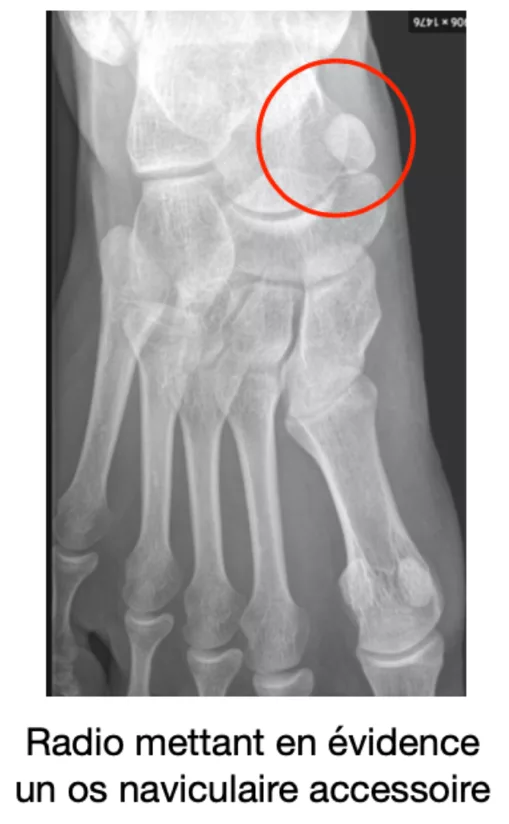

L’os naviculaire accessoire est un petit os surnuméraire situé juste à côté de l’os naviculaire, sur le bord interne du pied, au niveau de l’arche plantaire. Il est incorporé dans le tendon du muscle tibial postérieur, qui joue un rôle crucial dans le maintien de la voûte plantaire.

La plupart des gens ignorent qu’ils possèdent cet os jusqu’à ce qu’un traumatisme (entorse de la cheville), le port de chaussures inadaptées ou une activité physique intense déclenche une inflammation. Elle se manifeste par une bosse osseuse visible, une rougeur et une douleur lors de la mobilisation.